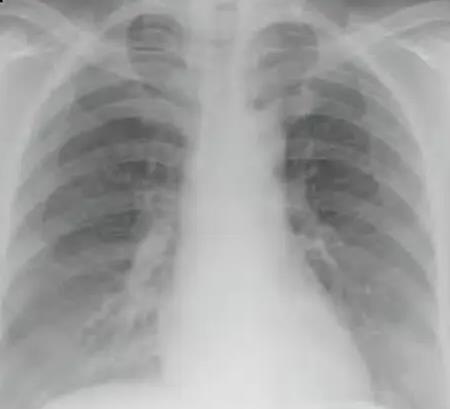

“白肺”是什么?有什么癥狀?專家提醒這些人群即使沒有發(fā)熱也要注意

近日,部分新冠病毒感染者在診療過程中發(fā)現(xiàn)了肺炎,甚至肺部CT出現(xiàn)了“白肺”現(xiàn)象?!鞍追巍笔鞘裁??有什么癥狀?可以治愈嗎?會留下后遺癥......